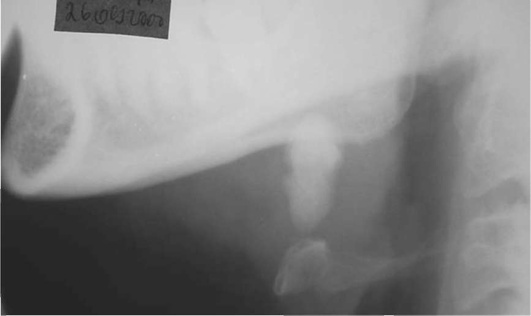

Диагностика. В распознавании слюннокаменной болезни имеет значение не только обнаружение камня, но и выявление причины камнеобразования. Анамнестический признак в виде слюнной колики в 99% случаев позволяет предположить наличие конкремента. На обзорных рентгенограммах рентгеноконтрастные камни хорошо визуализируются (рис. 6.11-6.13), на сиалограммах они видны в виде очага дефекта наполнения контрастного вещества. На эхосиалограммах камни видны по типу «звуковой дорожки». Особенно часто (более чем в 99%) камни выявляются на компьютерных томограммах.

Рис. 6.12. Рентгенограмма нижней челюсти в боковой проекции. В области левой поднижнечелюстной железы определяется конкремент